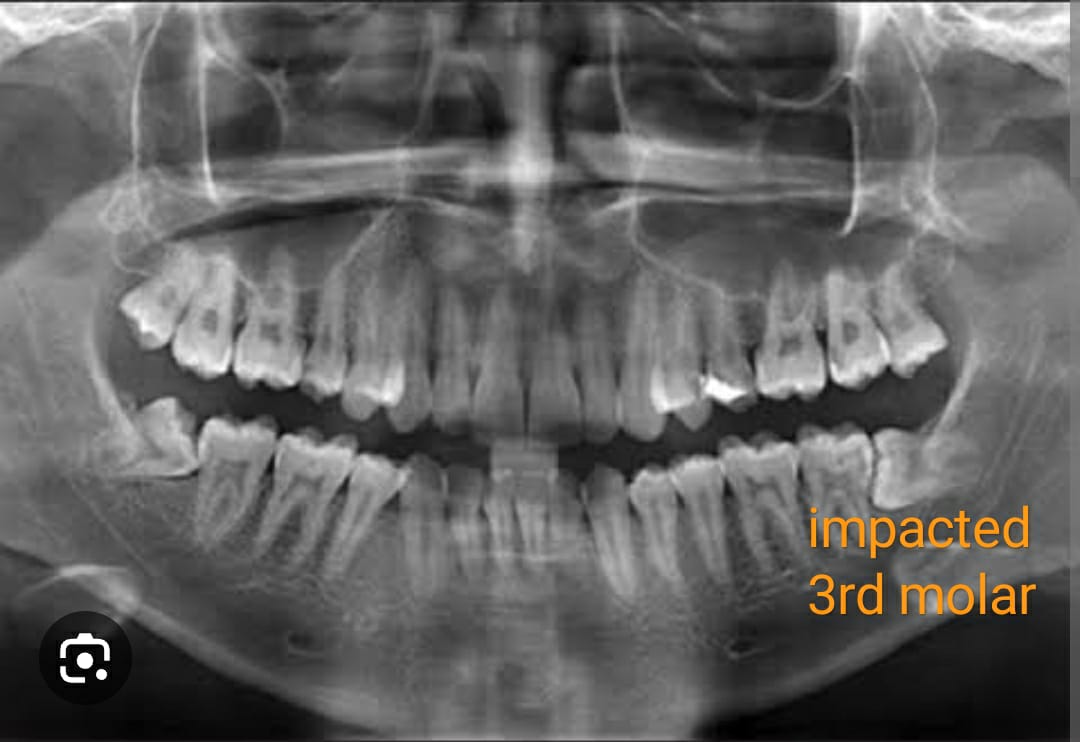

In the bustling city of Mumbai, Rhea Malhotra was a young, ambitious marketing professional in her mid-twenties, carving out a promising career path. However, beneath her confident demeanor, she was battling a silent yet relentless adversary—her wisdom teeth. For months, Rhea endured the discomfort of impacted wisdom teeth, which began to affect both her personal and professional life.

Rhea's story is not an isolated one. Many young adults between the ages of 18-30 experience similar issues with their wisdom teeth. Typically, these teeth emerge in the late teenage years or early adulthood, often leading to overcrowding or misalignment within the mouth. For Rhea, the pain was more than just physical; it was a constant, nagging reminder that disrupted her daily activities, interfered with her work, and dampened her social life.

She discovered that wisdom teeth extraction is a common and effective solution for alleviating pain and preventing future dental complications. The procedure, though initially intimidating, promised not only relief from her current discomfort but also a future free from dental distress. Rhea realized that by confronting her fears and opting for the extraction, she could reclaim her life from the grips of her dental woes.

Rhea’s journey highlights the profound impact that resolving dental issues can have on a person’s overall well-being. Wisdom teeth extraction is more than just a dental procedure; it's a gateway to a more comfortable, confident life. For individuals like Rhea, who face the dual challenges of pain and emotional distress from impacted wisdom teeth, taking that step towards extraction can be life-changing.

In conclusion, if you or someone you know is dealing with the discomfort of impacted wisdom teeth, consider the long-term benefits of extraction. Like Rhea, you too can find relief and rediscover the joy in your daily life. Don’t let the fear of a procedure hold you back from achieving a pain-free future. Embrace the change and take the first step towards a healthier, happier you.